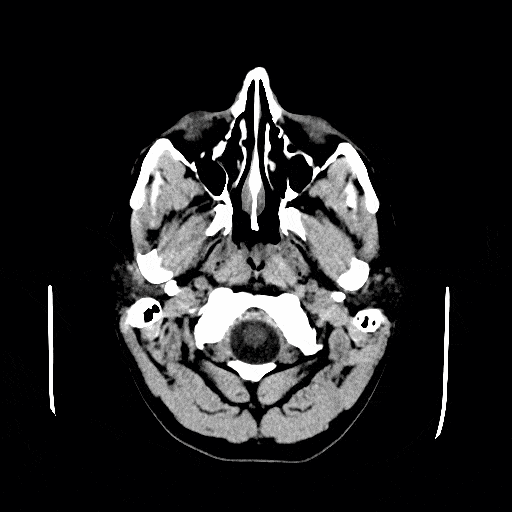

Computed tomography (CT) scanning is an extremely common imaging modality in modern medicine. With advancements in technology, it is rapidly replacing many diagnostic radiographic procedures. In this article, we will outline the basic science behind CT scans, describe the principles of interpretation, and highlight their advantages and drawbacks compared to other imaging techniques. Pro Feature - 3D Model You've Discovered a Pro Feature Access our 3D Model Library Explore, cut, dissect, annotate and manipulate our 3D models to visualise anatomy in a dynamic, interactive way. Learn More Basic Principles CT scans are created using a series of x-rays, which are a form of radiation on the electromagnetic spectrum. The scanner emits x-rays towards the patient from a variety of angles – and the detectors in the scanner measure the difference between the x-rays that are absorbed by the body, and x-rays that are transmitted through the body. This is called attenuation. The amount of attenuation is determined by the density of the imaged tissue, and they are individually assigned a Hounsfield Unit or CT Number. High density tissue (such as bone) absorbs the radiation to a greater degree, and a reduced amount is detected by the scanner on the opposite side of the body Low density tissue (such as the lungs), absorbs the radiation to a lesser degree, and there is a greater signal detected by the scanner. Conventional x-rays provide the radiographer with a two-dimensional image, and require the patient to be moved manually to image the same region from a different angle. In contrast, because of the advanced mathematical algorithms involved with CT, the three-dimensional planes of the human body can be imaged and displayed on a monitor as stacked images, detailing the entirety of the field of interest. This is accomplished by acquiring projections from different angles and through a process known as reconstruction, the three-dimensional data is viewable on a two-dimensional monitor. The data collected can theoretically never be a perfect replica of what is being scanned, but is a close enough representation to be used for medical diagnostic purposes. By Timeholder (Own work) [CC BY 3.0], via Wikimedia CommonsFig 1In CT scanning, three-dimensional planes of the human body can be imaged and displayed on a monitor as stacked images, detailing the entirety of the field of interest. Contrast Imaging Depending on the structure being imaged, CT scans can be used with and/or without contrast. The introduction of an intravenous radiofluorescent contrast into the bloodstream can be used for a variety of diagnostic purposes, for example: Used to visualise the cardiovascular system (e.g. investigating for suspected aneurysms, dissections, or atherosclerotic diseases). Used to identify whether a tumour is malignant. After approximately 7 minutes after an intravenous injection with iodinated CT contrast, the contrast begins to expel from the body via the urinary system. The contrast can be seen in the ureters going into the bladder creating a CT Urogram; a procedure that is commonly replacing the traditional intravenous pyelogram seen in radiography. Oral contrast can also be administered if investigation is required of the digestive system. (Crohn’s disease, bowel obstruction, diverticulitis, appendicits). By James Heilman, MD (Own work) [CC BY-SA 3.0], via Wikimedia Commons Figure 2Contrast enhanced CT scan, demonstrating an abdominal aortic aneurysm Interpreting a CT scan Orientation When interpreting at CT scan, it is important to determine the orientation. Images are most commonly presented in the transverse plane, and are orientated so that we are looking up the body from the patient’s toes. A helpful way to get your bearings is the acronym RALP. Starting at the 9 o’clock position and moving clockwise in 90 degree intervals, we are looking at the Right, Anterior, Left and Posterior aspects of the patient. Radiologists will often use images reconstructed in the coronal and sagittal plane to help supplement their diagnosis. The Image The density of the body tissue determines the degree to which the x-rays are attenuated. In turn, this affects the brightness and contrast of the imaged tissues. Those tissues with high attenuation coefficients (strong absorption) show up white, and those which absorb with low attenuation coefficients (weak absorption) show up black. This is quantified by the Hounsfield Scale of radiodensity. Tissues with a high Hounsfield score have a high attenuation coefficient, and so appear white: Substance Hounsfield Value Air -1000 Fat -70 Water 0 Blood 70 Bone 1000 Clinical Relevance Intracranial bleeds Intracranial bleeds are potentially life-threatening conditions, and occur most commonly as an acute or delayed response to trauma. They can occur spontaneously from the rupture of cerebral aneurysms, but this is less common. CT scanning has evolved to become to mainstay of investigation of patients with a suspected intracranial bleed. There are four broad types of intracranial bleed: By TeachMeSeries Ltd (2025) Fig 1.1CT scan of a massive extradural haematoma Extradural: A bleed outside the dura mater, which creates a lentiform (lemon shaped) bleed on CT. These are arterial, and frequently related to blunt trauma. There may be a midline shift. Subdural: A bleed between the dura and arachnoid layers, most commonly due to a tearing of the bridging veins in the elderly. These can become symptomatic up to a month after the initial insult. These create crescenteric lesions on head CT, with a possible midline shift. Subarachnoid: A ruptured aneurysm in the subarachnoid space leads to a subarachnoid haemorrhage, although they can be a consequence of trauma. Their radiographic features can be subtle; the CSF becomes paler as it becomes tinted with blood, and the normally dark subarachnoid cisterns turn white. Intracerebral haemorrhage: Causes include hypertension, diabetes, and trauma. They present on CT angiography as localised lesions, with surrounding oedema due to inflammation. Comparison to Other Imaging Techniques CT scanning is the ideal imaging modality in emergency cases. It is often the choice of examination for trauma patients in the emergency room (due to its quick scan times). It is more efficient when an immediate diagnosis is required such as intracranial bleeds, dissection of a blood vessel, or renal stones. The biggest drawback of CT is that it utilises radiation that can potentially be harmful, especially with younger patients and children. However, the benefits often outweigh the risk, and there has been an upward trend in the use of CT in diagnostic imaging. Technological advancements in CT have paved the way for more advanced applications – such as virtual colonoscopy – which is quickly replacing traditional barium enema studies. Cardiac gating on CT scanners have allowed institutions to perform studies dedicated to the cardiac arteries and to perform measurements of ejection fraction. Specialised software has advanced 3D applications in CT, allowing for better visualisation of certain pathologies. Below is a summary table of the common imaging modalities. Depending on the tissue being imaged, the urgency of the investigation and the level of detail required, any of these techniques may be preferred. Factor CT (CT abdo used as example) MRI X-ray (CXR used as example) Ultrasound Duration 3-7 minutes 30-45 min 2-3 min 5-10 minutes Cost Cheaper Expensive Cheap Cheap Dimensions 3 3 2 2 Soft tissue Poor detail Excellent detail Poor detail Poor detail Bone Excellent detail Poor detail Excellent detail Poor detail Radiation 10mSv None 0.15mSv None Do you think you’re ready? Take the quiz below Pro Feature - Quiz Computed Tomography (CT) Scanning Question 1 of 3 Submitting... Skip Next Rate question: You scored 0% Skipped: 0/3 1800 More Questions Available Upgrade to TeachMeAnatomy Pro Challenge yourself with over 1800 multiple-choice questions to reinforce learning Learn More Rate This Article